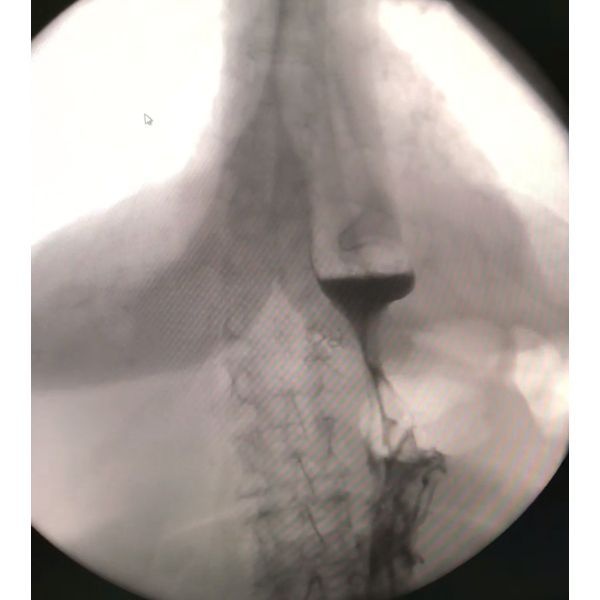

Через неделю ей сняли швы и провели контрольную рентгеноскопию:

- контраст свободно поступал в желудок при любом положении тела;

- скорость дальнейшего продвижения контраста в 12-перстную кишку соответствовала норме;

- пищеводно-желудочный переход находился под диафрагмой;

- кардиальный (верхний) отдел желудка не выходил в грудную полость.